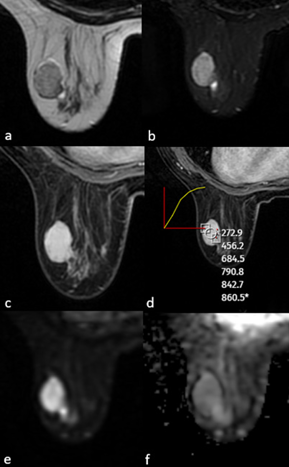

18 (72%) CFAs and 19 (76%) PTs showed heterogeneous enhancement in early sequences after contrast administration. However, on delayed phase T1WI, 10 (40%) of the CFAs and 18 (72%) of the PTs sustained heterogeneous enhancement characteristics. This finding was noted as statistically significant (p=0.023). Signal intensity / time curve demonstrated type one pattern in majority of the cases, 18 (72%) of the CFAs and 17 (68%) of the PTs. seven (28%) CFAs and seven (28%) PTs had type 2, one (4%) PT had type 3 pattern. Among CFAs, one (4%) had enhancing and 18 (72%) had non-enhancing internal septations, whereas among PTs, four (16%) of them were enhancing and 16 (64%) were non-enhancing. Pseudocapsulation was seen in 12 (48%) of the CFAs and seven (28%) of the PTs. Two(8%) CFAs and nine (36%) PTs had cystic components and this result was also statistically significant (p=0.017, Table 2). MRI examples of CFA and PT are shown in Figures 1 and 2.

Figure 1. MRI of a 28-year-old female patient showed a well-circumscribed solid mass with no contour lobulation, hypointense on T1WI (a), heterogeneously hyperintense on T2A (b), homogeneous internal structure, homogeneous contrast enhancement on postcontrast T1WI (c), type 1 signal intensity/time curve (d) and no significant diffusion restriction on DWI (e,f). After excision, the pathological diagnosis was fibroadenoma